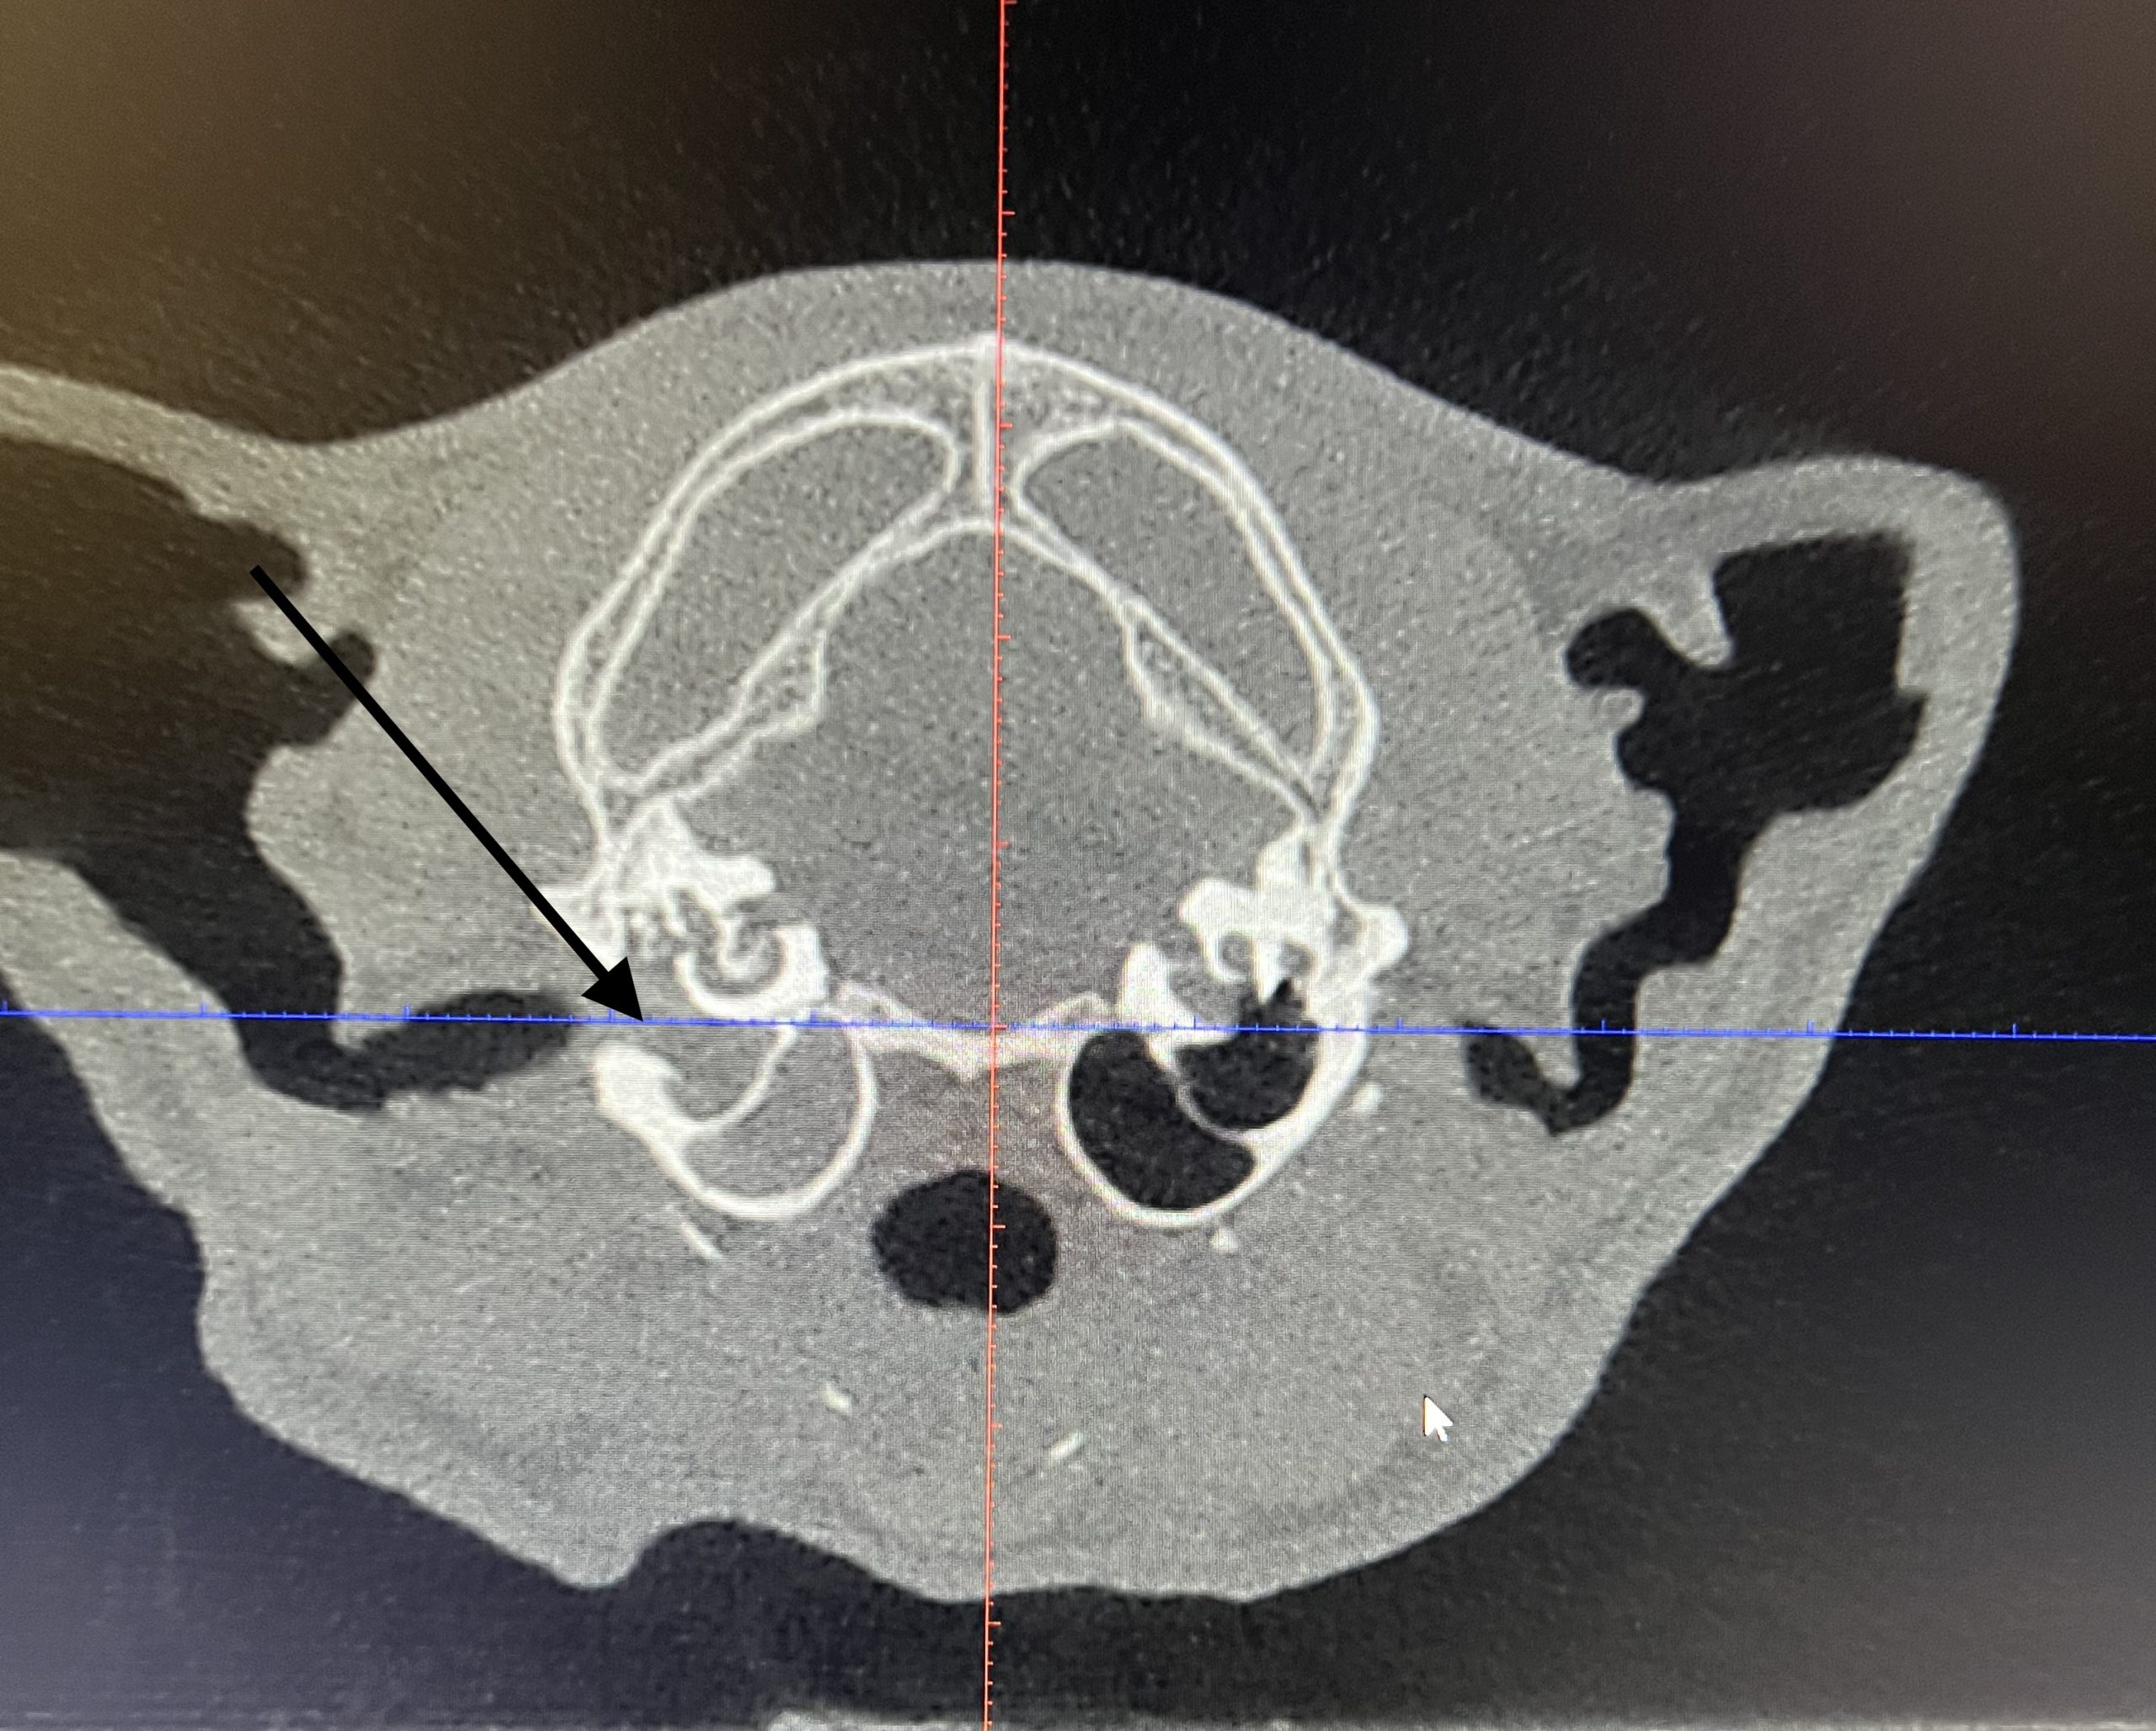

CBCT-röntgen (DT-röntgen) eller skiktröntgen är en avancerad röntgen som skapar 3-dimensionella bilder av skallen och mellanöronen. Utan denna diagnostik kan man inte se graden och omfattningen av förändringar i mellanörat. Vi har en så kallad CBCT (Verity Vet) som är en mindre CT lämpad just för denna diagnostik. Bildkvaliteten är mycket hög och ger detaljgranskning av de små vävnadsstrukturerna i örat. Vid CBCT räcker det att djuret får lugnande medicin. Scanningen tar inte mer än 40 sekunder. Vi läser av de flesta bilderna direkt men i vissa fall skickas de för extern granskning till radiolog (röntgenspecialist).

CT-röntgen (DT-röntgen) eller skiktröntgen är en avancerad röntgen som skapar 3-dimensionella bilder av skallen och mellanöronen. Utan denna diagnostik kan man inte se graden och omfattningen av förändringar i mellanörat. Vi har en så kallad CBCT (Verity Vet) som är en mindre CT lämpad just för denna diagnostik. Bildkvaliteten är mycket hög och ger detaljgranskning av de små vävnadsstrukturerna i örat. Vid CBCT räcker det att djuret får lugnande medicin. Scanningen tar inte mer än 40 sekunder. Vi läser av de flesta bilderna direkt men i vissa fall skickas de för extern granskning till radiolog (röntgenspecialist).

CBCT är en form av skiktröntgen (datortomografi) för skalle. Vid CBCT skapas 3D-bilder och man kan med hög skärpa se de små skelettdelarna som finns i mellanörat som hörselbenen eller trumhinnan.